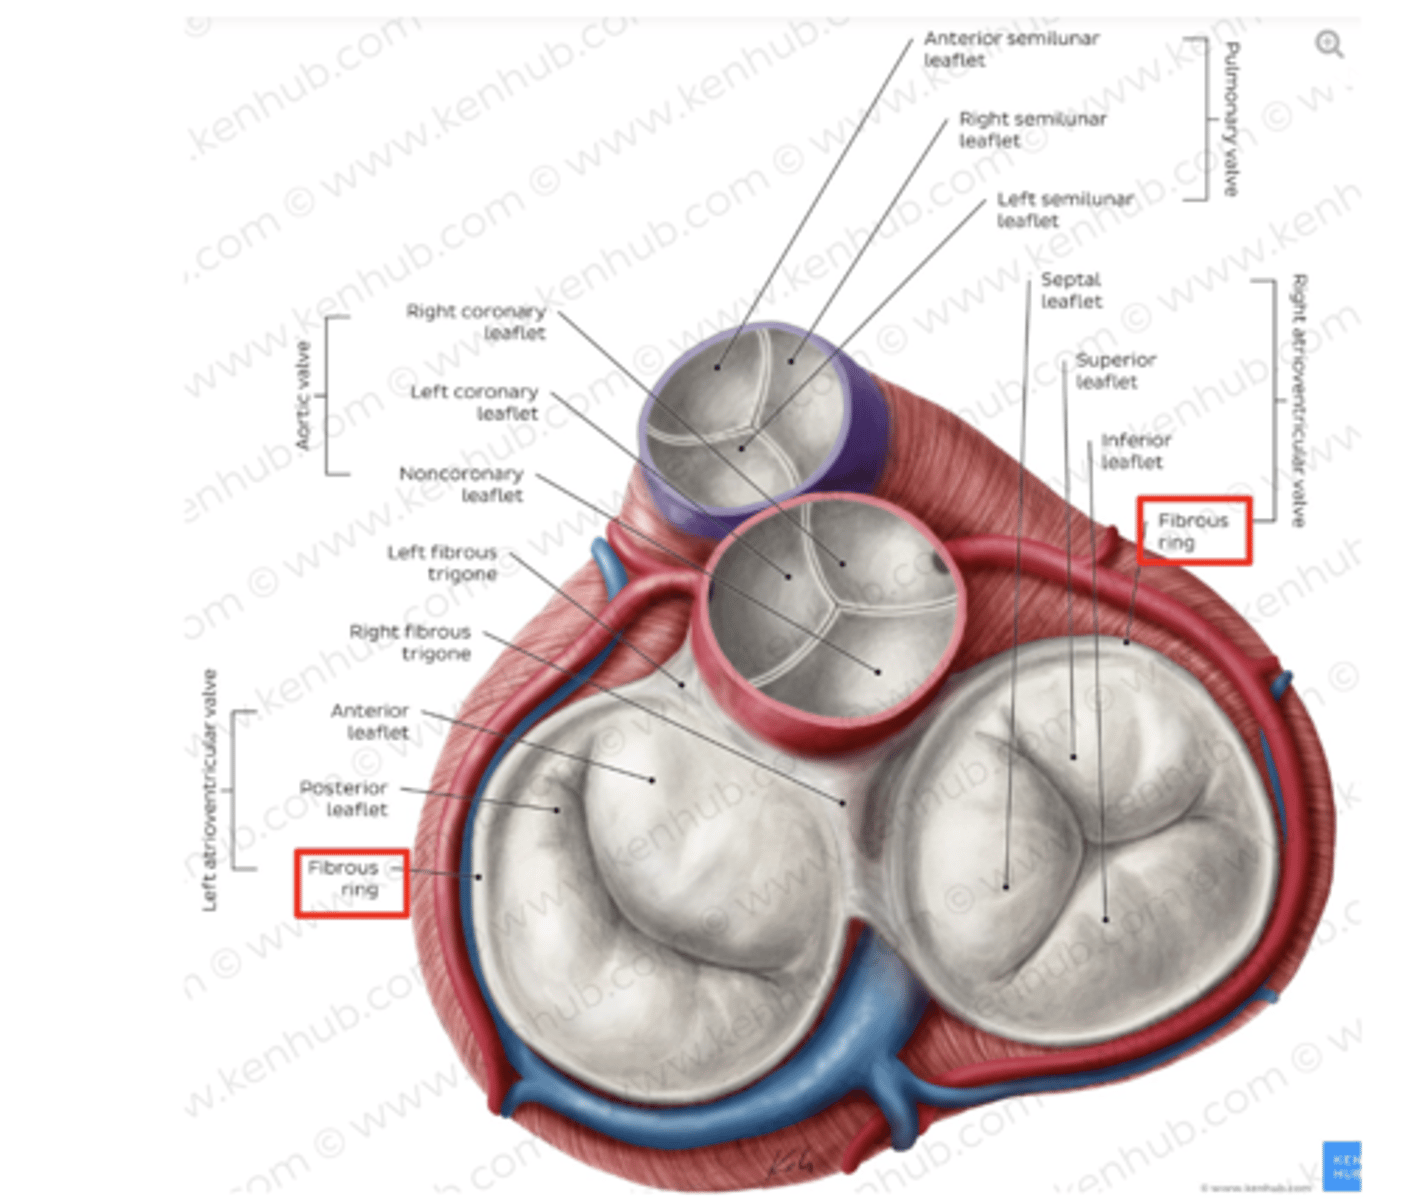

What are the valves separating atrium and ventricle?

. Tricuspid valve (right atrioventricular valve, 3 cusps)

. Mitral or bicuspid valve (left atrioventricular valve, 2 cusps)

What are the 3 cusps of the tricuspid valve?

Anterior

Posterior

Septal

What are the positions of the pulmonary valve cusps?

Anterior

Right

Left

What is the valve in the AV left canal?

. Mitral valve

2 cusps (anterior and posterior) and 2 associated papillary muscles

What is the valve to prevents reflux in the aorta?

Aortic valve

What are the 3 parts of the aortic valve?

3 semilunar cusps

posterior

right

left

POSITION IS DIFFERENT THAT IN THE PULMONARY (posterior vs anterior)

What are the four valves in the heart?

Tricuspid

Mitral or bicuspid

Pulmonary

Aortic

What are other functions of the rings in the cardiac skeleton?

maintain the shape of the openings between the heart's chambers

insertion site for the cusps of the valves and muscular heart tissue.

What are the components of the cardiac skeleton?

. pulmonary ring,

. aortic ring

. AV rings

RINGS ARE IN THE SAME PLANE AROUND THE VALVES